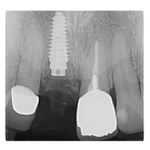

治療途中のインプラント症例

治療途中のインプラント症例です。 主訴 歯がグラグラして揺れる 年齢 52歳 男 ...